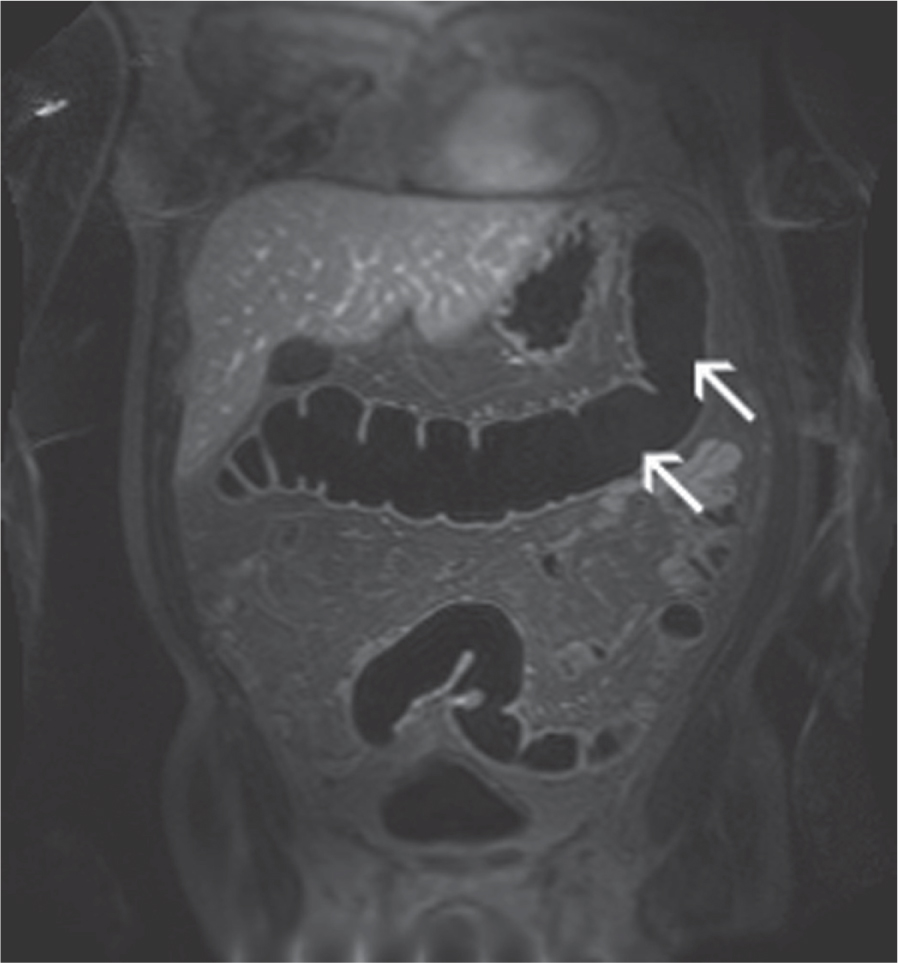

From www.researchgate.net

Woman 54 y with right colon cancer. Pre surgical MRI study In A (SPACE Imaging Techniques Colon Cancer Crc testing is divided into two categories: Anatomical imaging techniques remain the backbone for management, with computed tomographic (ct) imaging for colon. The development and introduction into clinical practice of new anatomical and functional imaging techniques and advanced. This paper will review recent developments in imaging technologies and the evolving roles for these techniques in. In the last several years,. Imaging Techniques Colon Cancer.